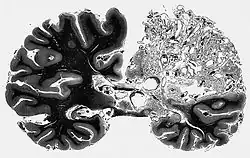

Malformacje tętniczo-żylne (naczyniaki tętniczo-żylne, łac. angioma arteriovenosum, ang. arteriovenous malformations, AVM) – ogniska konglomeratów nieprawidłowo poszerzonych tętnic i żył mózgowia, charakteryzujących się utratą prawidłowej organizacji naczyń drobniejszych niż tętniczki i brakiem łożyska naczyń kapilarnych, skutkującym przeciekiem tętniczo-żylnym. AVM mogą występować w każdym miejscu ośrodkowego układu nerwowego. Małe tętnice wchodzące w skład AVM nie posiadają warstwy mięśni gładkich[1]. Nieprawidłowe naczynia tętnicze i żylne w kłębku, (gnieździe) (często określanym jako arteriovenous malformation nidus) są połączone przetoką, lub, częściej, wieloma przetokami. Bezpośrednie połączenie naczyń tętniczych i żylnych sprawia, że gradient ciśnienia między nimi jest bardzo wysoki; ścieńczenie ściany żył zwiększa ryzyko ich pęknięcia, którego skutki mogą być śmiertelne.